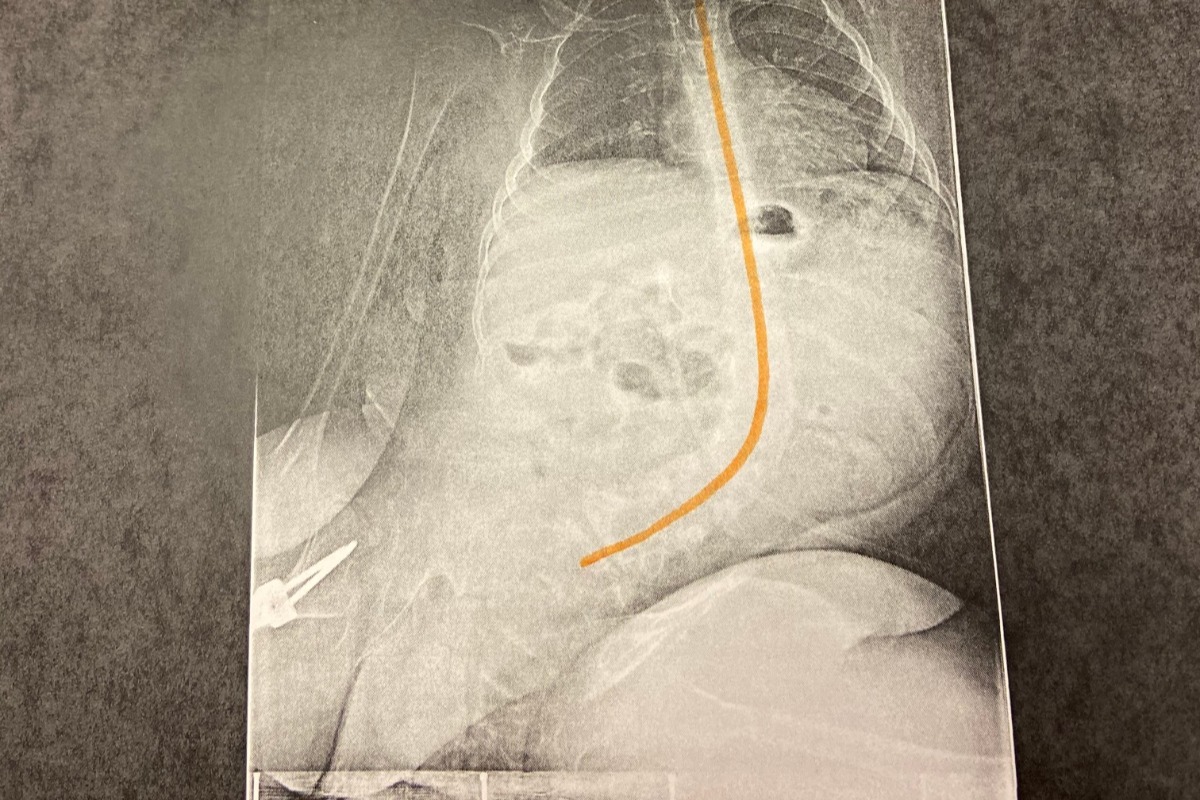

Beau is currently scheduled to have his sixth surgery on February 11, 2020; which will attempt to correct the severe curvature (scoliosis) of his spine. His spine has slowly contorted to the point where his doctors deem it almost inoperable. During this operation, the doctors will be fusing two titanium rods on either side of Beau’s spine to help make his spine straighter. The doctors estimate they can only correct 50% of what the degree is at. His spine is currently curved at 56%. He will be in the hospital for about 14 days for recovery from the surgery, and once released he will require several additional months for a complete recovery. Because Beau is a special needs child, he sometimes requires more time for the recovery process than other children require.

(X-ray of Beau's Spine)

Beau is currently scheduled to have his sixth surgery on February 11, 2020; which will attempt to correct the severe curvature (scoliosis) of his spine. His spine has slowly contorted to the point where his doctors deem it almost inoperable. During this operation, the doctors will be fusing two titanium rods on either side of Beau’s spine to help make his spine straighter. The doctors estimate they can only correct 50% of what the degree is at. His spine is currently curved at 56%. He will be in the hospital for about 14 days for recovery from the surgery, and once released he will require several additional months for a complete recovery. Because Beau is a special needs child, he sometimes requires more time for the recovery process than other children require.

(X-ray of Beau's Spine)